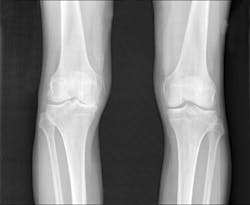

"Patients are frequently in pain by the time osteoarthritis is diagnosed. The imaging tests most frequently used, x-rays, don't indicate the level of pain or allow us to directly see the amount of cartilage loss, which is a challenge for physicians and patients," says co-first author Averi A. Leahy, B.A., an MD/Ph.D. student in the medical scientist training program at TUSM and the Sackler School.